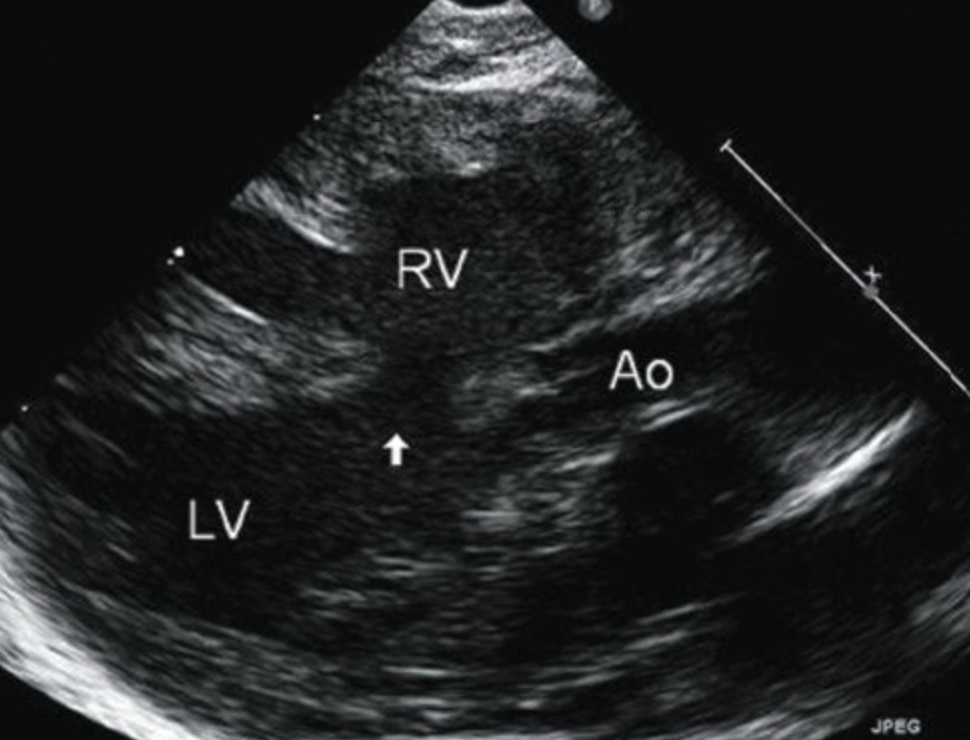

17

Q

What is this? Be Specific

A

Muscular VSD